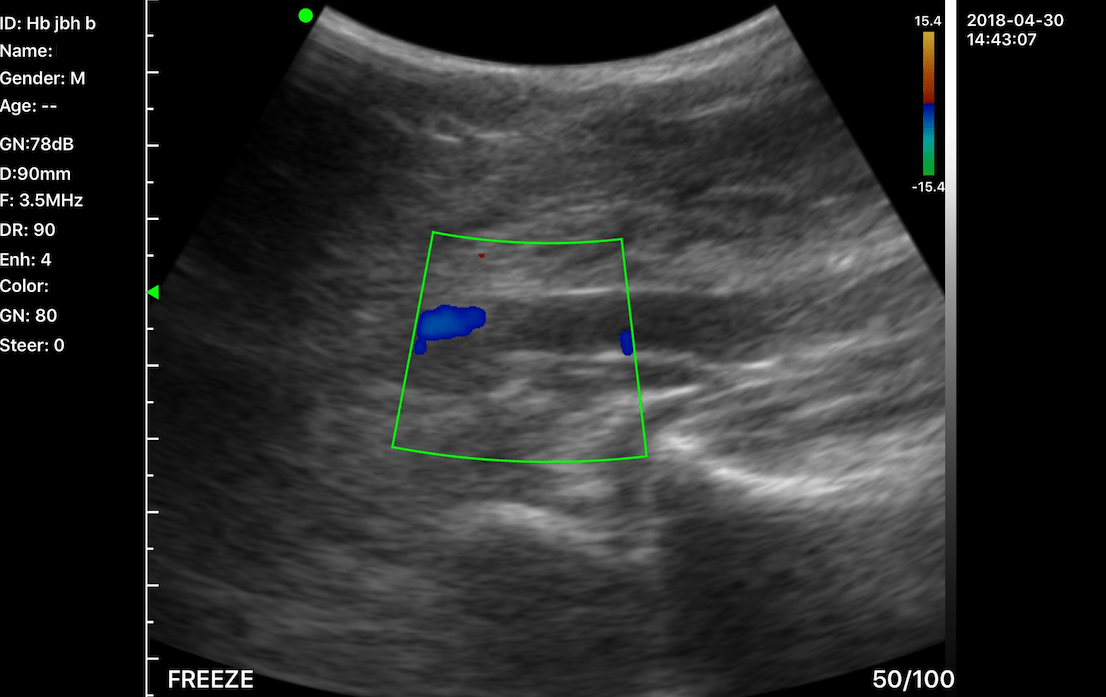

C10MT 3.5-5.0Mhz Convex B&W, Colour Portable Ultrasound.

The new C10MT Colour Doppler Hand Held Ultrasound probes with 128 element 24 frame per second frame rate gives real imaging performance for any application.

Functions:  Many functions found on larger real time ultrasound system can be found on the Wireless US such as: adjusting gain, dynamic range, focus position, depth, colour mode & sensitivity. The linear probes offer steer function in colour mode. There is also a biopsy mode which applies an adjustable guiding line for needle angle guide. On screen measurements can be done using the calliper setting were anchoring or moving measurement cursors with your finger or a stylus.

• Display mode: B, B/M, colour, PW, PDI